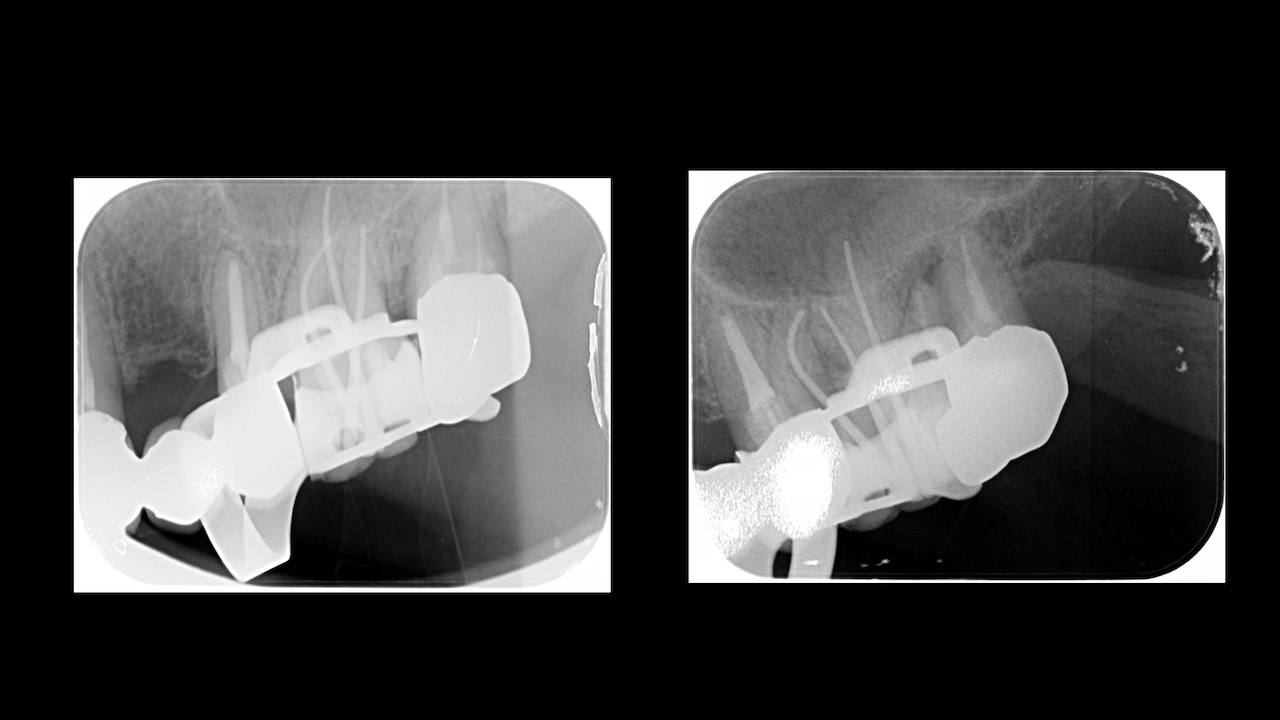

次は横浜からお越しのF先生。

口腔外科出身で外科治療が好きな?先生だ。

Sinus tractがある歯牙の再根管治療だ。

DB根はすでに切断されている。

が、逆根充がなされていない。

DBは根切済みだ。

Pにも病変がある。

ということは、再根管治療だろう。

ただ、予後はGuardedだ。

なぜか?根切がうまく行っていないからだ。

臨床的にDB

この後、

Sinus tractは消失した。

3ヶ月経過した。

DBの病変が小さくなっている。

Pは病変が大きくなっていうように見えるがまだわからない。

ということで、切ることだけが全てでないということを証明してくれた。

このまま経過を追いましょう。

また、Advanced 2026でその結果を教えてください。